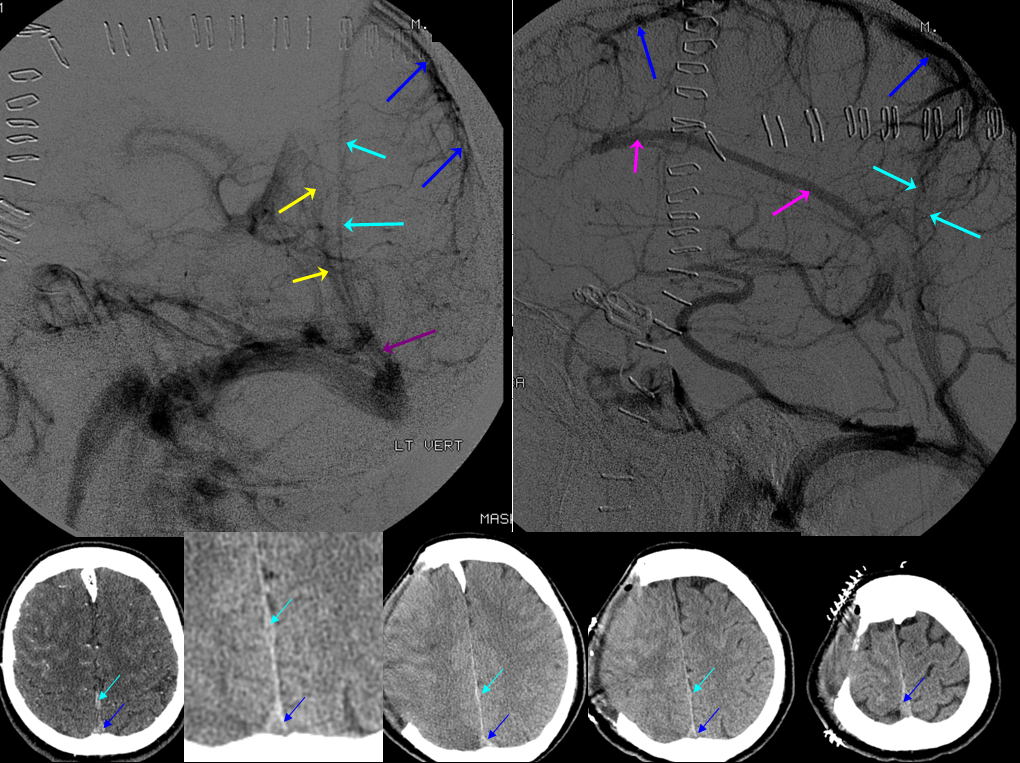

Below is a case of severe venous sinus thrombosis and secondary parenchymal venous infarcts

The explanation for the above tragic pattern is below. On the right, sigmoid and transverse sinuses are patent. However, the Labbe is hypoplastic, and majority of outflow used to go to the Trolard, into the now occluded SSS. There is no other effective way to go — the trolard tries to decompress via a left diploic vein, and convexity tries to access the deep venous system (which normally should not be well-seen in setting of hypoplastic right A1 segment). The left situation is much better, as well-developed superficial sylvian veins drain into the patent Cavernous Sinus. Thus, despite thrombosis of the left transverse and sigmoid sinuses, the left hemisphere is doing better, while the right one, which has patent transverse and sigmoid sinuses, is devastated.

Post venous thrombectomy — with limited results. Note presence of same left diploic vein as seen in right ICA injection, and connection between the distal superior sagittal sinus and the deep venous system via the inferior sagittal sinus.